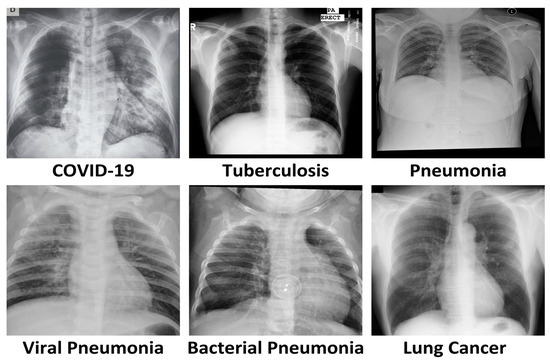

The growing number of lung-related diseases is causing a significant increase in the risk of illness and mortality rates [13]. The COVID-19 outbreak, which began in late 2019, has brought to light the importance of lung health. The disease primarily affects the lungs, causing severe damage and respiratory issues, including pneumonia. The pandemic has emphasized the critical need for early and accurate detection of lung diseases. A chest X-ray (CXR) is a medical test that uses a very small amount of ionizing radiation to create grayscale images of the inside of the chest. These images can only be interpreted by a radiologist or physician. The test is used to evaluate the lungs, heart, and chest wall and may help diagnose symptoms like shortness of breath, coughing, fever, chest pain, or injury. It can also aid in diagnosing and monitoring the treatment of various lung conditions like pneumonia, emphysema, and cancer. Due to its speed and ease, it is especially useful in emergency situations [14]. As shown in Figure 1, there are various chest X-rays available that indicate different lung diseases. Figure 1 displays various chest X-rays depicting different lung diseases.

Figure 1. Showing different images taken from different datasets [15,16,17,18,19].